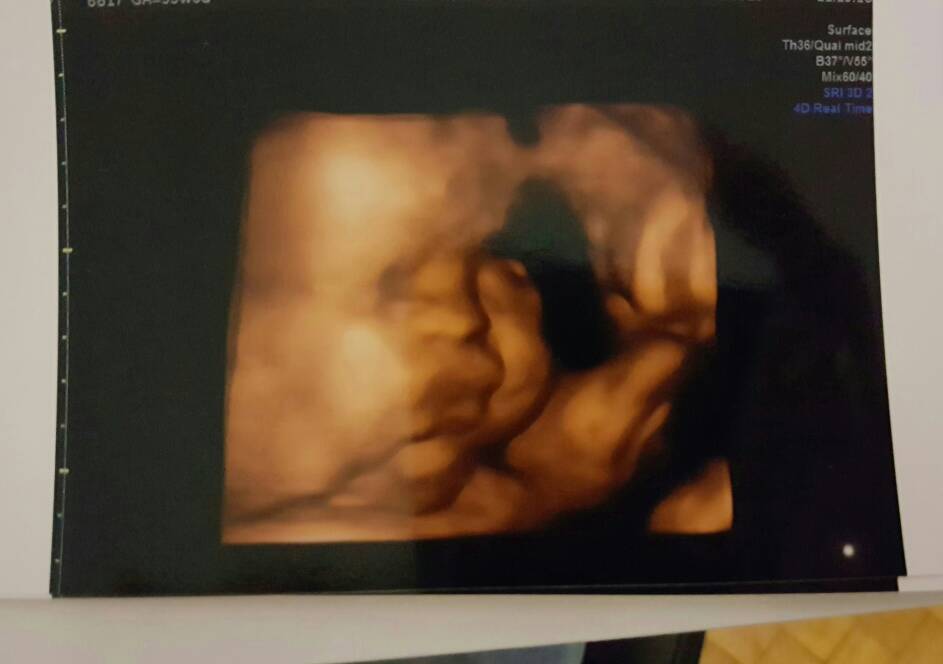

Malutki ma się dobrze, wszystkie pomiary ok,mieści się we wszystkich normach, poza wagą

straszny z niego pulpecik, zresztą same zobaczcie.